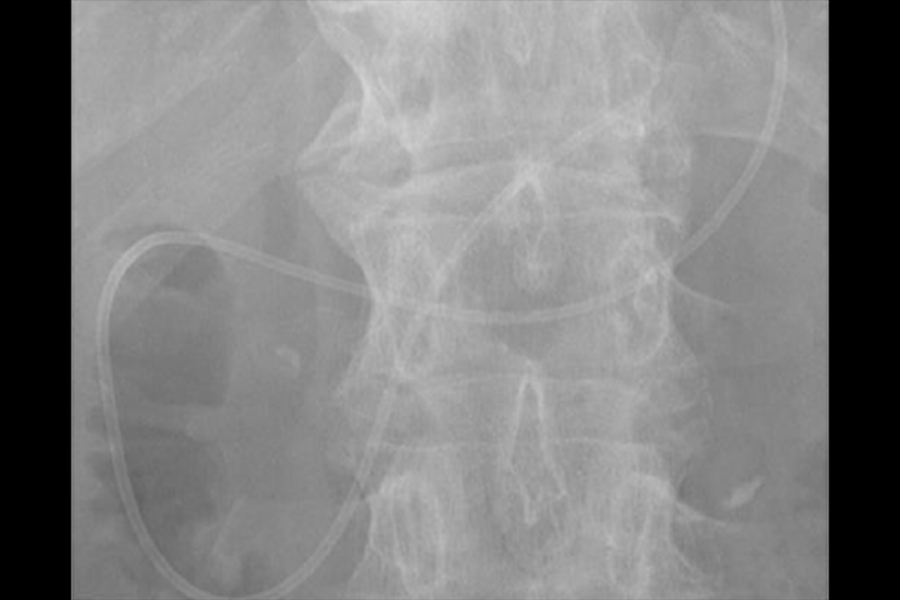

内視鏡的逆行性胆道膵管造影(ERCP)は、内視鏡を口から入れて十二指腸まで進め、胆管や膵管にカテーテルを挿入して造影剤を注入し、胆道・膵管のレントゲン撮影を行う検査です(図1)。

これにより結石や腫瘍といった胆管や胆嚢、膵管の異常を詳しく調べることができます。近年では画像診断の進歩により、超音波検査やCT、MRIでも胆道や膵管の情報が得られるようになってきていますが、悪性の病気が疑われた場合にはERCP実施時に胆道や膵管の細胞や組織を採取して病理検査を行うことがあります。また、胆管・膵管の狭窄に対してプラスチックや金属のステント(筒状のもの)を挿入して、胆汁や膵液の流出障害を改善させる治療を行うことがあるほか(図2)、胆管結石や膵石に対しては内視鏡で取り除く治療も行うことができます(図3)。このようにERCPは胆膵領域の診断、治療に重要な役割を担っています。